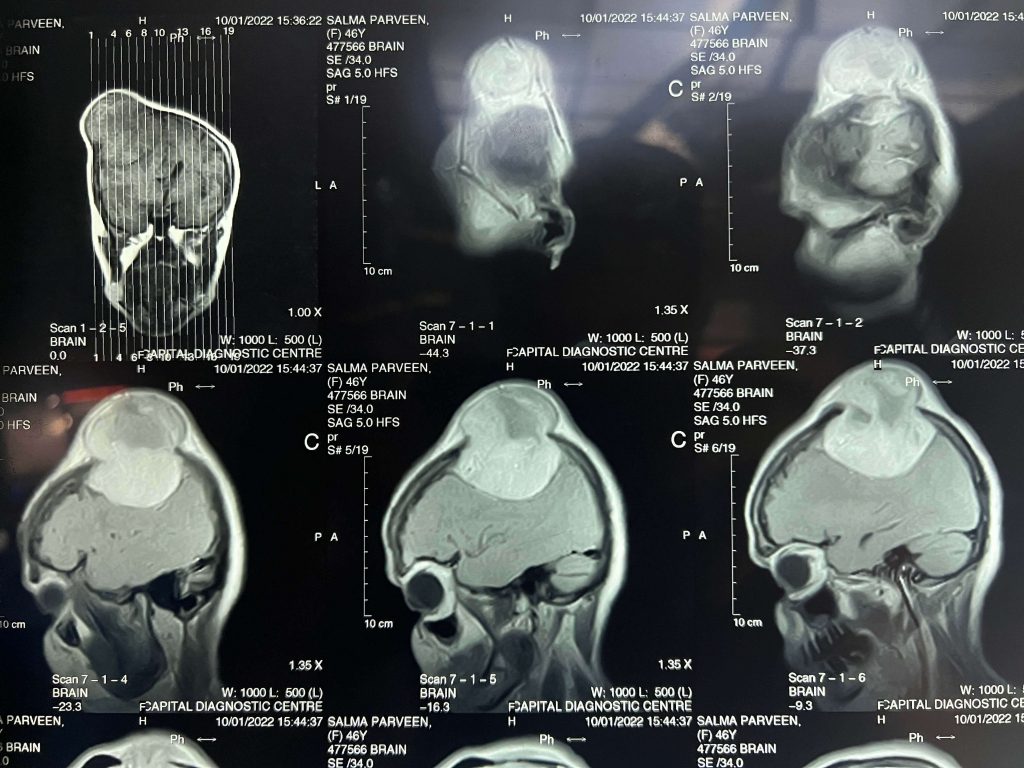

Brain Tumors Overview

- Meningiomas

- Gliomas

- Pituitary Tumors

- Posterior fossa tumors

- Orbital Tumors(Eye)

- Ventricular tumor

- Brain Cysts